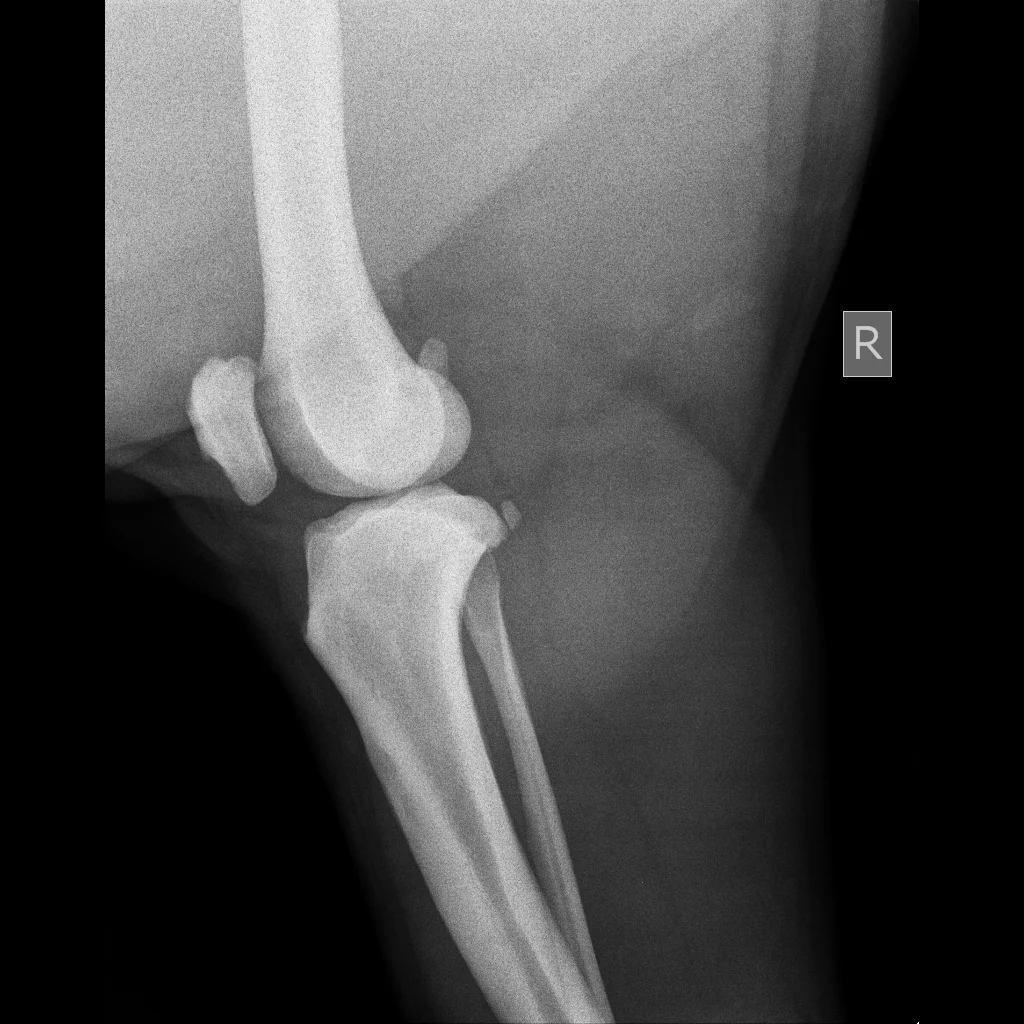

The two photos below show two stifle joints (knees) of a bear at the Chengdu Bear Rescue Centre. You can see the difference between the two, the L labelled joint has spiky pieces and haziness around the edge of the bone in the joint, these changes are secondary to DJD.